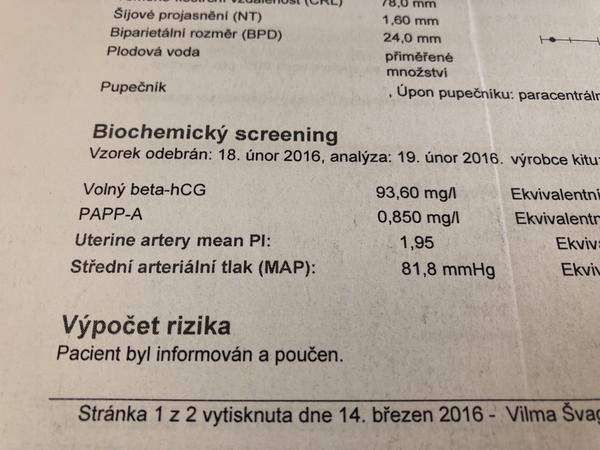

@basice Diky, to Mom zrovna nevim.. u te druhe hodnoty je to nad 60/70 pry holcicika..Ale koukam u

@jednaholkaa Tady jsem schválně našla ty výsledky z předchozích těhotenství 🙂 Obě to jsou holky 🙂 A hodnoty nízké 🙂 Teď zatím hodnoty nevím, na screening jdu ve čtvrtek :D